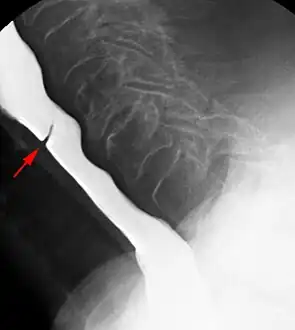

Esophageal web stenosis in barium swallow examination lateral view.